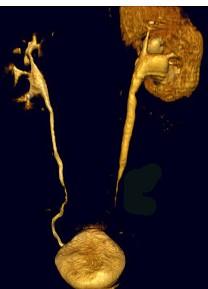

问题 男,59岁,反复尿频尿急尿痛4年余,尿常规检查:红细胞(+),白细胞(++),CT扫描如图示,下列说法正确的是 ( )

选项 A.左侧输尿管中下段输尿管管壁增厚,管腔狭窄 B.左侧侧输尿管上段扩张 C.考虑为输尿管结核 D.考虑为慢性输尿管炎 E.考虑为输尿管移行细胞癌

答案 ABD